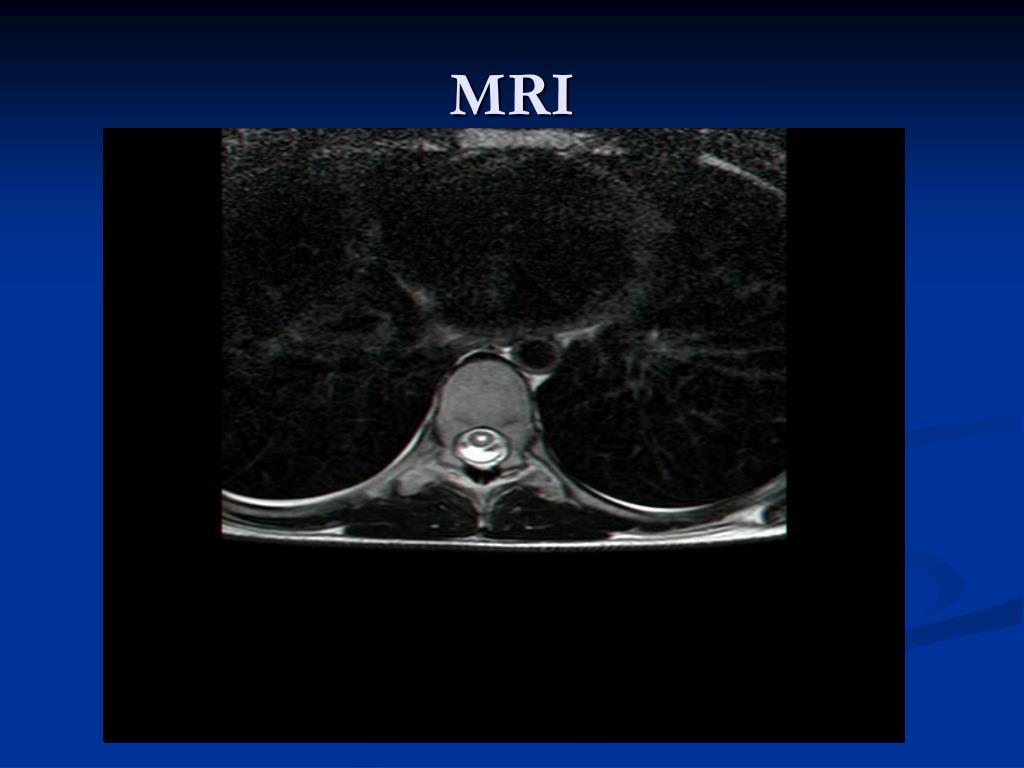

4. MRI

5. MRI

6. MRI

15. WNV MYELITIS = WNV POLIOMYELITIS-LIKE SYNDROME Acute and asymmetric flaccid paralysis occurs in about 10% of the patients who are hospitalized for WNV infection. Neurological lesion is localize in the anterior horn motor neurons. CSF-moderate pleocytosis of few hundred lymphocytes, protein is moderately elevated , glucose is normal. MRI of the spinal cord – high signal intensity on T2-weighted scans in anterior horns .